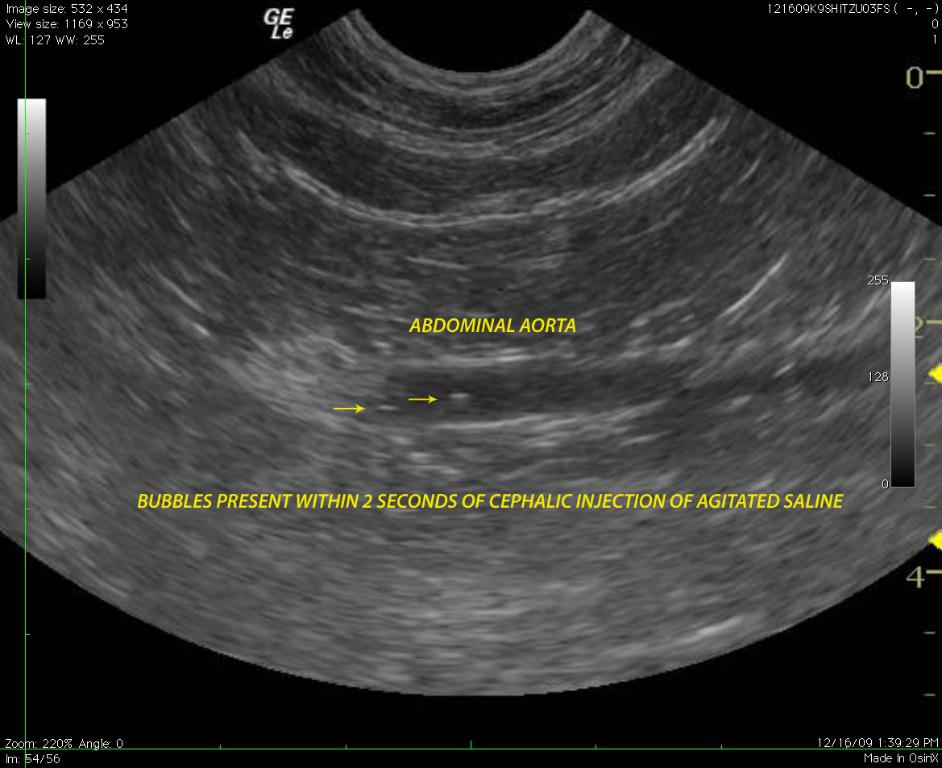

A 6-year-old FS Shih Tzu presented for exercise intolerance and cyanosis under stress. The clinical exam was otherwise unremarkable. A slight right and left sided murmur was auscultated. Right sided cardiomegaly was noted on radiographs. Radiographs (Image 1): generalized right sided cardiomegaly is noted. There is no evidence of pulmonary congestion. The lung pattern is unremarkable.